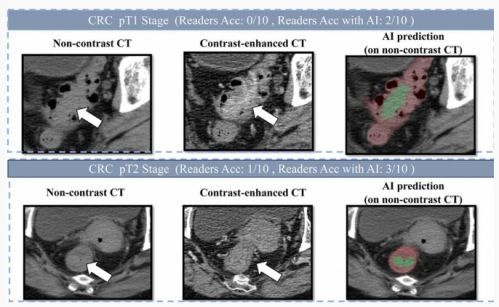

为克服肠道内容物对影像的干扰,达摩院的技术团队采用了 “先定位、后诊断” 的深度学习架构,并专门针对小于 3 厘米的早期肿瘤进行训练。这种两阶段的学习策略,使得 AI 模型能够有效地分割复杂的肠道区域,从而更准确地检测出可疑病灶。

DAMO COCA 模型通过深度学习技术,能在常规 CT 影像中识别早期肠癌。